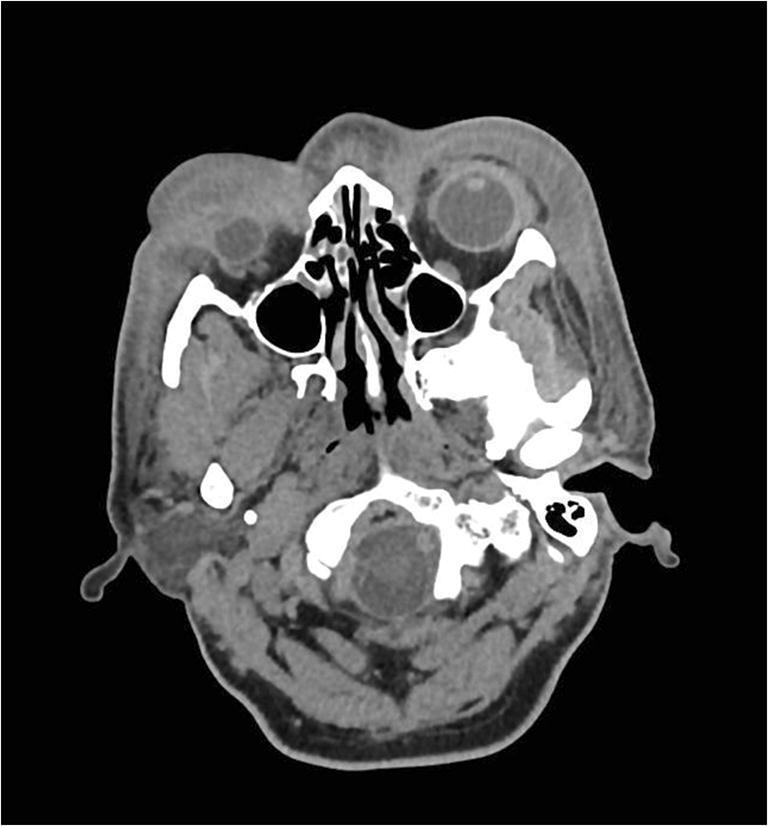

眶周坏死性筋膜炎:从发病到重建历程

Necrotizing fasciitis of the periorbital region: from presentation to reconstructive journey.

Periorbital necrotizing fasciitis is a very rare condition with a UK incidence of 0.24 cases per million per annum. Outcomes can range from disfigurement to sight loss and even death. Debridement is crucial when sight or life is threatened and the subsequent reconstructive stages can be challenging. We describe two cases of periocular necrotizing fasciitis demonstrating the progression of the disease as well as the surgical debridement for both pre-septal and post-septal disease and the reconstructive steps leading to outcome. Level of evidence: Level V, therapeutic study.

眶周坏死性筋膜炎是一种非常罕见的病症,在英国每年的发病率为百万分之0.24例。其后果可能从毁容到视力丧失甚至死亡。当视力或生命受到威胁时,清创术至关重要,而随后的重建阶段可能具有挑战性。我们描述了两例眼周坏死性筋膜炎病例,展示了疾病的进展情况以及针对眶隔前和眶隔后疾病的手术清创术以及导致最终结果的重建步骤。证据级别:V级,治疗性研究。